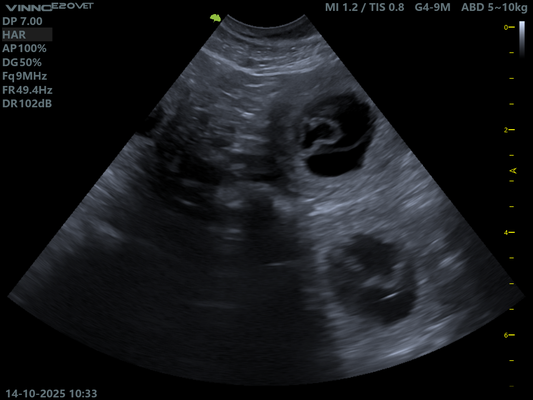

14.10.2025 Ultraschall Untersuchung.

Schon nach einem kurzen Blick in Ruby's Bauch war klar.

Sie ist tragend!

Doch wie viele es werden bleibt bis zuletzt spannend.

Hier müssen wir uns absolut keine Sorgen machen. Ruby scheint einen normalen Wurf zu erwarten, so auch die Aussage unserer Tierärztin.